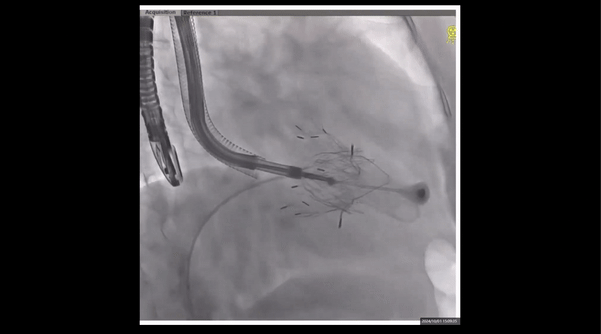

術(shù)前右室造影

夾持件位置確認(rèn)

室間隔位置確認(rèn)

術(shù)中經(jīng)食道超聲輔助下可見(jiàn)LuX-Valve Plus夾持件抓捕瓣葉狀態(tài)良好,夾持件在位,室間隔錨定位置良好,假體瓣膜整體錨定狀態(tài)穩(wěn)固。